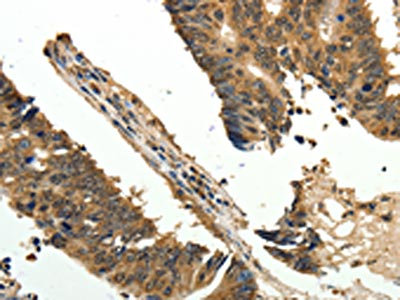

The image on the left is immunohistochemistry of paraffin-embedded Human thyroid cancer tissue using CSB-PA546739(ODC1 Antibody) at dilution 1/30, on the right is treated with fusion protein. (Original magnification: ×200)

The image on the left is immunohistochemistry of paraffin-embedded Human colon cancer tissue using CSB-PA546739(ODC1 Antibody) at dilution 1/30, on the right is treated with fusion protein. (Original magnification: ×200)